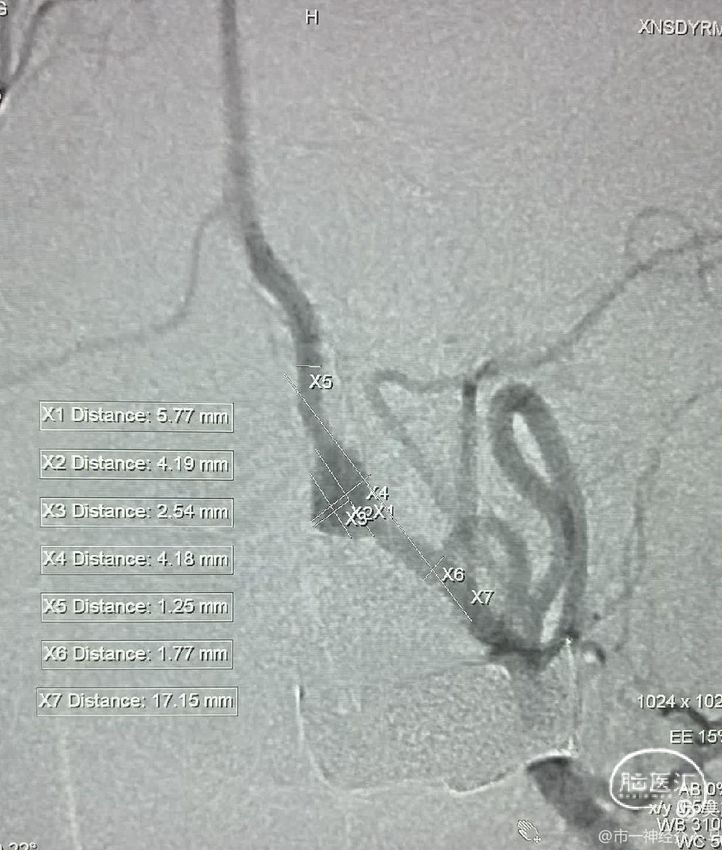

快速行头颈部CTA显示罪魁祸首是左侧椎动脉颅内段夹层动脉瘤,动脉瘤呈三角形,基底很宽,进深很浅,根据经验,动脉瘤凸起部分只是冰山一角,往往凸起部分的对侧及远近端血管都会受到病变累及。

该病例病变侧椎动脉是非优势侧,对侧椎动脉比较发达,且汇入基底动脉,对远端的基底动脉及小脑上动脉、大脑后动脉供血很充分。

该手术怎么做更合理?风险更小?短时间之内必须要考虑清楚的,用一个编织支架或密网支架辅助,可以把动脉瘤凸起部分栓塞掉,从而能保住病变所在的椎动脉,这似乎是最合理的手术方案,也是大部分人能接受的方案。